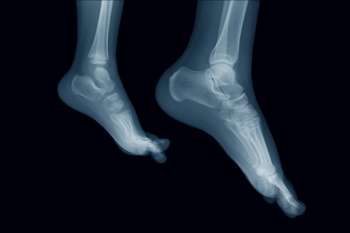

In many cases the cause of toe pain is obvious, but in others, a podiatrist may want to use more advanced methods to determine the problem. These can range from simple visual inspections and sensation tests to X-rays and MRI scans. Prior medical history, family medical history, and any recent physical traumatic events will all be taken into consideration for a proper diagnosis.

Treatments for toe pain and injuries vary and may include shoe inserts, padding, taping, medicines, injections, and in some cases, surgery. If you believe that you have broken a toe, please see a podiatrist as soon as possible.